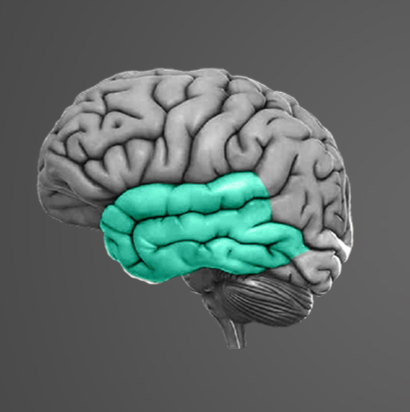

-

Question of

Určete:

-

žíly

-

tepny

-

vejcovody

-